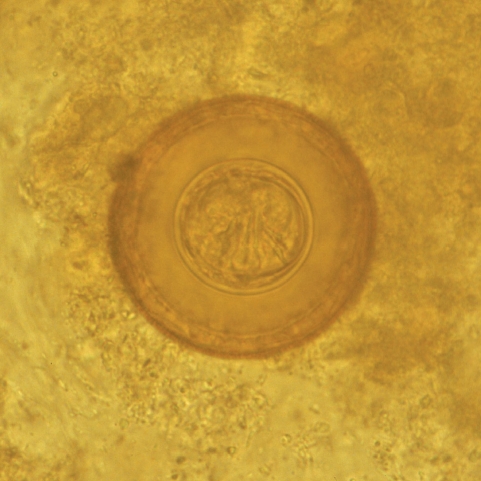

Before the child being referred to the Outpatient Clinic of the Paediatric Clinic of the University Hospital of Catania, the proglottids and several stool samples had been examined in a private laboratory and the child was diagnosed with Dipylidium caninum infection. Therefore, he was treated by his general practitioner with mebendazole for 3 days, without achieving clinical remission. A second stool examination, carried out in the same private laboratory after 20 days, revealed the presence of the same parasite, which led to a further treatment with a prolonged cycle of mebendazole (3 days per week for 3 consecutive months). One month after the end of the latest therapeutic cycle, the child was brought to the parasitological laboratory of the University Hospital in Catania, presenting remittent fever (maximum peak 37.7℃), abdominal pain, diffuse cutaneous itching, transient thoracic rash, and arthromyalgias. Blood and urine examinations together with abdominal ultrasound scan were performed without showing any abnormal results. Also, the parasitological examination of concentrated stool samples was negative. Two weeks later, while the same symptoms were persisting, the child emitted again proglottids in his stool. A parasitological examination of a concentrated stool sample performed in our laboratory revealed numerous spherical eggs, 70 mm in diameter, which lacked polar filaments, and presented a thick-shelled outer membrane and a thin inner membrane containing 6 hooklets (Fig. 1) [2]. The child was admitted as an inpatient in our Paediatric Unit and treated with oral niclosamide (1 g on the first day and 500 mg/day for the following 6 days) [3]. Within a week from the start of niclosamide treatment, fever, arthralgias and diffuse itching completely recovered.